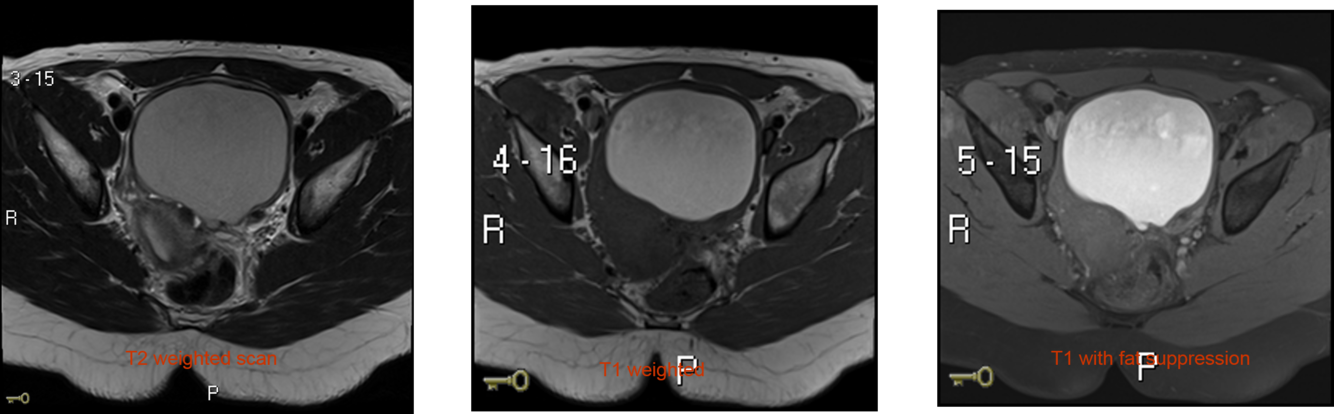

Describe the 2 main different types of MRI scan and what they look at

T1 images – 1 tissue type is bright – FAT e.g. subcutaneous fat (SC fat) and bone marrow

T2 images – 2 tissue types are bright – FAT and WATER e.g. CSF

Describe the appearnace of dermoid cysts on MRI

They can contain an admixture of many types of tissue, but most contain a large amount of fat.